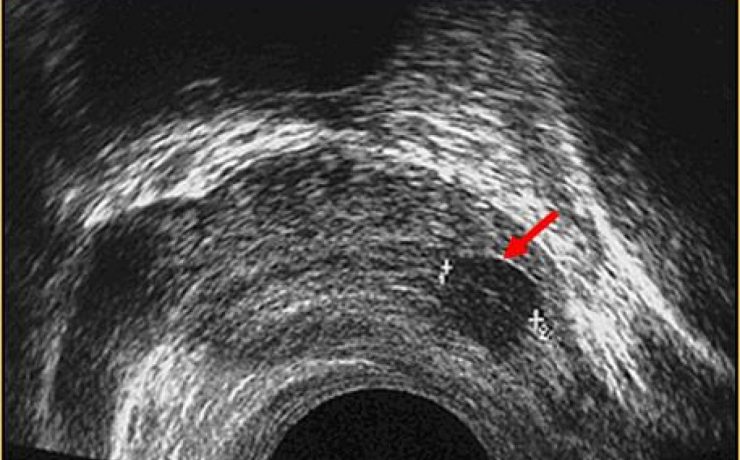

LA IMPORTANCIA DE LA ECOGRAFIA A LAS 11+0 A 13+6 SEMANAS DE EMBARAZO

Al principio, el ultrasonido en el primer trimestre se empezó a utilizar para medir la longitud cráneo-caudal del feto y estimar la edad gestacional, pero actualmente, además de eso, se evalúan varios detalles que permiten hacer una evaluación completa para identificar factores de riesgo que compliquen la gestación. Los objetivos